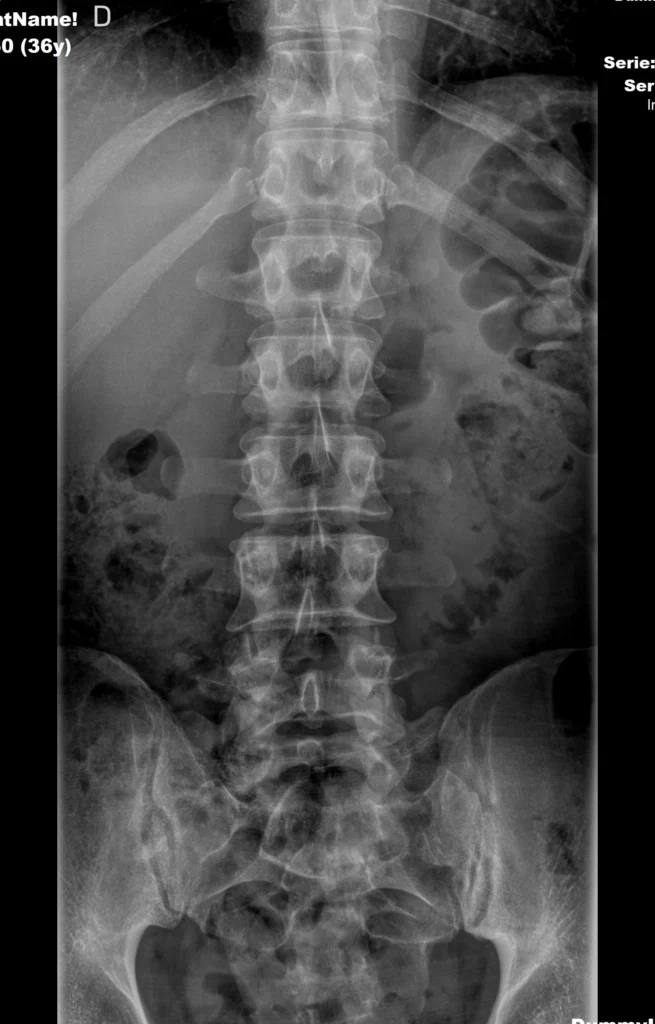

Densidad cálcica en radiografía de columna

Radiografía simple de columna lumbar utilizada como ejemplo docente para ilustrar la densidad cálcica del hueso.

Las estructuras óseas muestran alta atenuación de los rayos X, manifestándose como áreas radiopacas de color blanco.

- El hueso es claramente radiopaco

- Referencia para detectar calcificaciones anómalas

La densidad calcio no es exclusiva del hueso. En Radiología, el calcio se define por su alta capacidad de atenuación, independientemente de su localización anatómica.